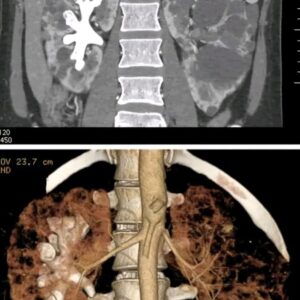

What Are Staghorn Kidney Stones>>>>>>

What Are Staghorn Kidney Stones? (Symptoms, Causes, and Treatment) Staghorn kidney stones are large, complex formations that resemble antlers and can significantly occupy the kidney’s renal pelvis….